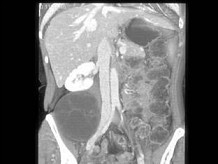

根据所提供的图像,最可能的诊断是()

• A.神经纤维瘤

• B.血肿

• C.脂肪肉瘤

• D.转移癌

• E.以上都不是